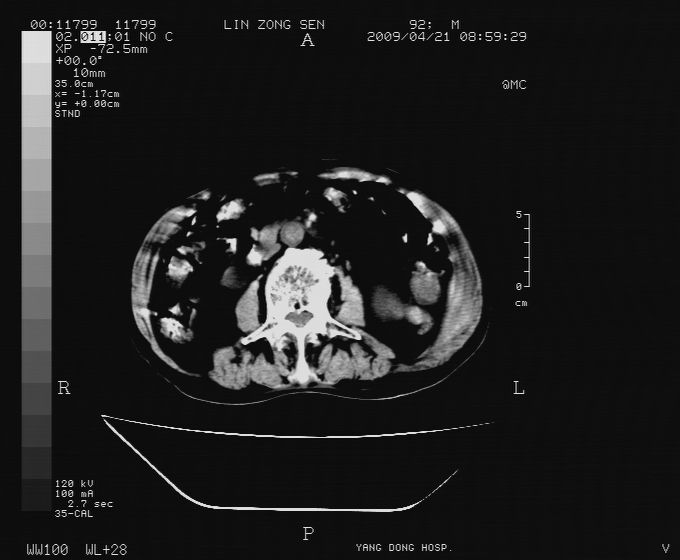

以下是引用卜一在2009-4-22 4:08:00的发言:[br]右肾积水伴输尿管上段积水!左侧肾多发囊肿!左侧腹壁软组织增厚,层次模糊,内密度较高—不排除血管瘤伴出血!